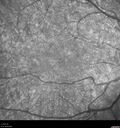

Ocular Lymphoma - Initially presented like auto-immune retinopathy280 views43 year old man: initial presentation - The vision in the left eye is blurry and opaque for about 2 weeks. In the central of the vision, when he covers the right eye, in the center of the left eye there is a film with a light in the middle. This has never happened before. He has not been sick for the last few months. A few weeks ago he saw waves on the floor when looking down but that has gone away. Since the vision loss started the vision has not changed much. The central vision is not getting better. Â

Labs normal. One positive antiretinal antibody - Arrestin

VA improved over 2 months to normal. Then the patient had 2 more episodes of self-limited vision loss (no treatment). Then 2 years later he presented with a diagnosis of CNS lymphoma and later developed subretinal deposits (last images)Oct 25, 2021